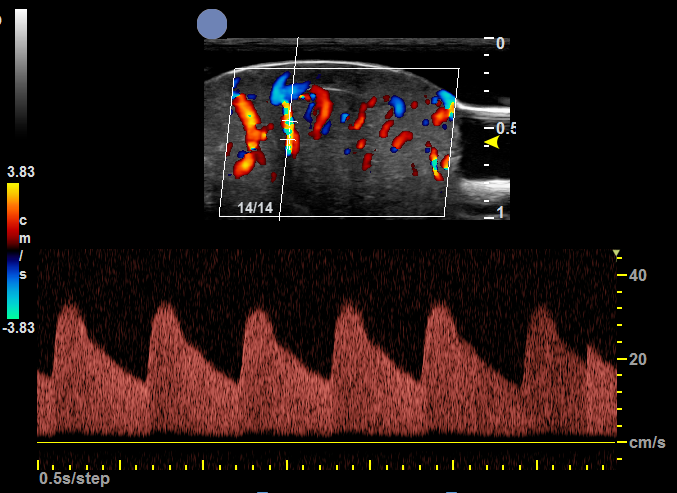

• 血管瘤与血管畸形

应用于血管瘤辅助诊断,可测量病灶大小及范围,浸润深度,区分动静脉,血管走行,定量测量血流流速,观测血管瘤瘤体内组织分布,鉴别自然病程(增殖期/稳定期/消退期)。

对于皮肤血管瘤和血管淋巴管畸形,超高频超声可以提供影像诊断和较明确的受累范围和层次判断,为制订治疗计划提供依据。通过治疗前后的高频超声影像对比,也可为治疗前后效果提供客观对比依据。

可用于先天性血管瘤、草莓状血管瘤、混合型血管瘤、静脉畸形、淋巴管畸形等。